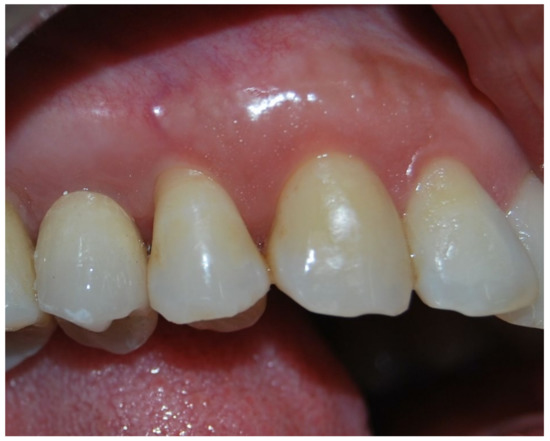

3. Results